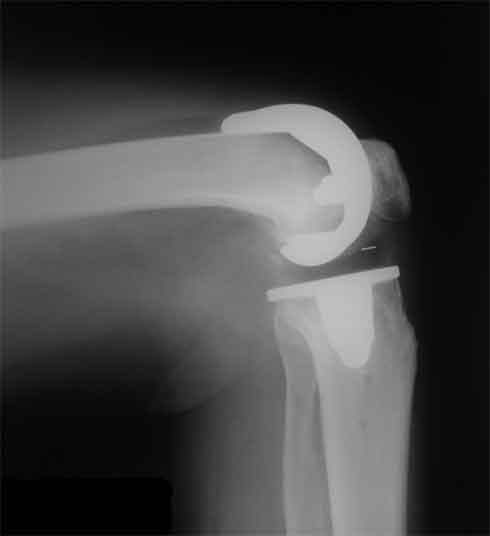

Оперирована пациентка 42 лет, избыточного веса. Выполнено б/ц протезированние коленного сустава эндопротезом LCS. Послеоперационный период гладкий, в срок 2 мес. после операции объем движений удовлетворительный, сгибание до острого угла, разгибание полное. В 3,5 мес. во время падения подвернула ногу, после чего появилась. клиника медиолатеральной нестабильности. В течении 3 недель фиксация в туторе. При повторном осмотре жалобы на дискомфорт в коленном суставе, «щелканье», неустойчивость в суставе. Вопросы/варианты дальнейшей тактики лечения пациентки.

1) Существует ли способы восстановления внутренней боковой связки на фоне протезированного коленного сустава и как добиться равномерного ее натяжения при всех углах сгибания.

2) Ревизия с установкой более связанного протеза (constrained)

3) Оставить как есть, ждать износа вкладыша, развития нестабильности протеза, а затем идти на связанный протез.

4) Другие варианты.